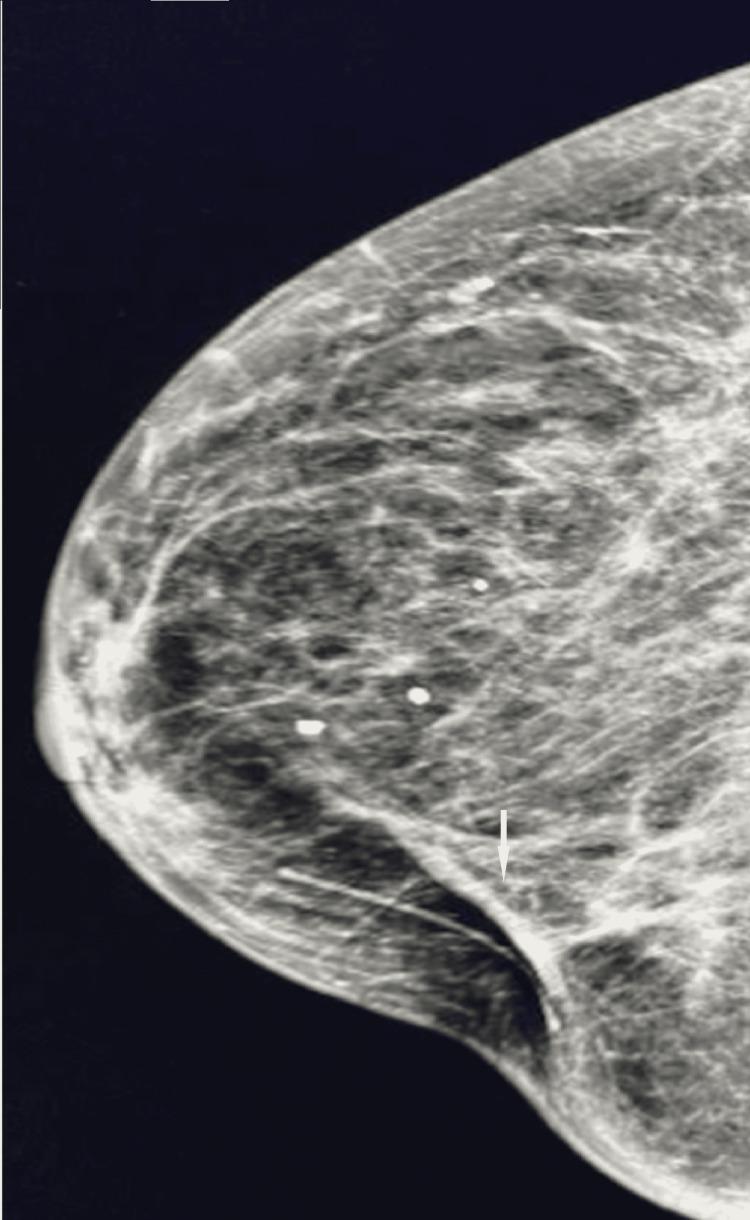

We describe a case of pathology-proven invasive lobular breast cancer (ILC) arising in a scar over 15 years after lumpectomy for previous invasive ductal carcinoma (IDC). The tumor was detected on screening mammography as a new focal asymmetry at the scar site and confirmed at diagnostic mammography. Ultrasound demonstrated an irregular, shadowing, hypoechoic mass at the scar site. Ultrasound-guided biopsy revealed poorly differentiated invasive lobular carcinoma. MRI and CT showed an irregular mass with pectoralis muscle invasion. Multimodality imaging findings are described. This is the first case to our knowledge reporting multimodality imaging findings of a breast cancer developing at the site of a surgical scar that is histologically different from the originally resected cancer.

我们描述了一例经病理证实的浸润性小叶乳腺癌(ILC)病例,该病例发生于先前因浸润性导管癌(IDC)行肿块切除术后15年以上的瘢痕处。肿瘤在筛查乳腺X线摄影中被检测为瘢痕部位新出现的局灶性不对称,并在诊断性乳腺X线摄影中得到证实。超声显示瘢痕部位有一个不规则、有阴影、低回声肿块。超声引导下活检显示为低分化浸润性小叶癌。MRI和CT显示有一个不规则肿块,侵犯胸大肌。描述了多模态成像结果。据我们所知,这是首例报告手术瘢痕部位发生的组织学上与最初切除的癌症不同的乳腺癌的多模态成像结果的病例。